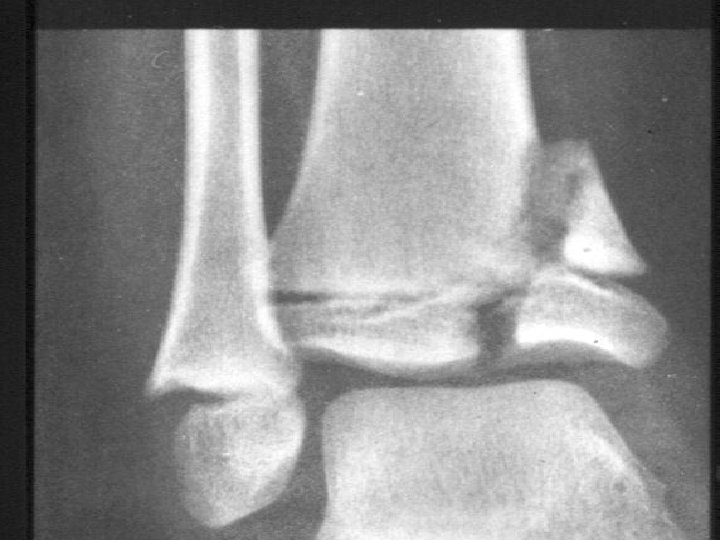

Fracture in children Physeal Injuries • 30% of the fractures and occurred twice as often in the upper extremities as in the lower extremities. • commonly used classification is that of Salter and Harris, which is based on the roentgenographic appearance of the fracture

Fracture in children